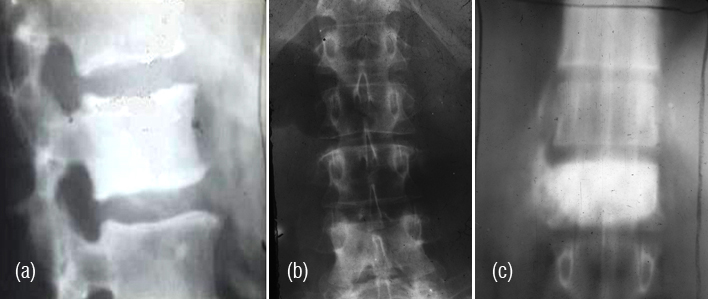

Radiologically, Sclerotic changes in the bone may be unifocal or multifocal. At times, lytic lesions may be also noted (Figure 8ab).

Figure 8: (a) Sclerotic myeloma – diffuse sclerosis of all the lumbar vertebrae. (b) Sclerotic lesion in the femur in Poems syndrome.